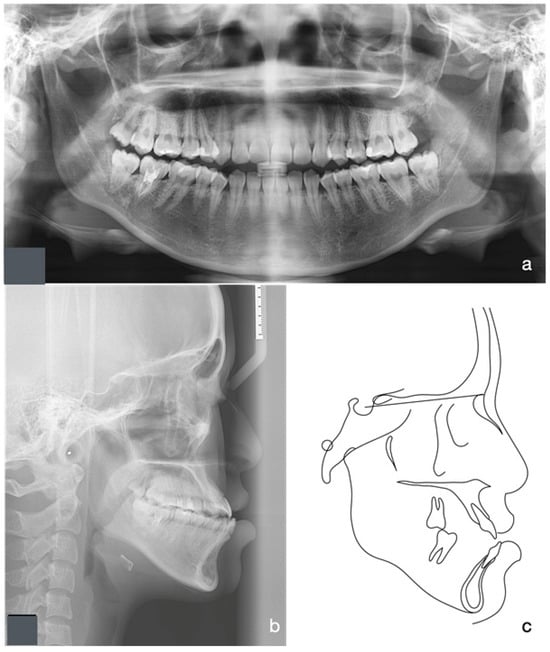

2.5. Treatment Results

2.4. Treatment Progress